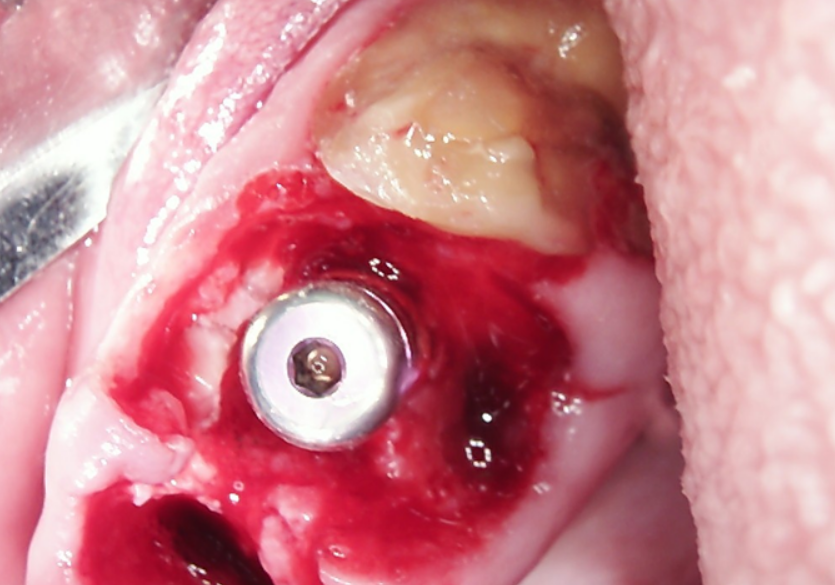

The presented images show the patient’s initial dental condition.

The implants were placed immediately following tooth extraction. They were positioned subcrestally — 2–3 mm below the bone crest — to allow for anticipated bone remodeling. A total of eight implants were placed in the maxilla and four in the mandible.

Placing the implants into the fresh extraction sockets allowed for optimal positioning for the future prosthetic restoration. The extractions were performed using the root shield technique, which is aimed at maintaining the thickness and height of the buccal and palatal bone walls. This technique, traditionally used for “conservation” even in case of delayed implantation, helps to minimize resorption and preserve the natural morphology of the alveolar ridge.